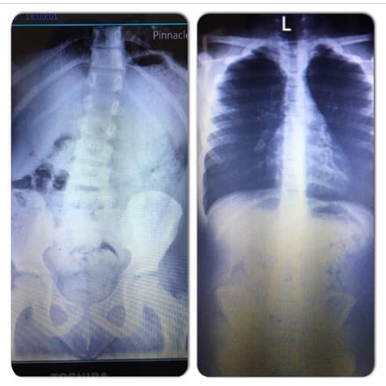

Faith - She was diagnoised with 16 degree scolosis. This is the Xray's Before Healing Prayer and After! - Give God the Glory! Prayer Works!